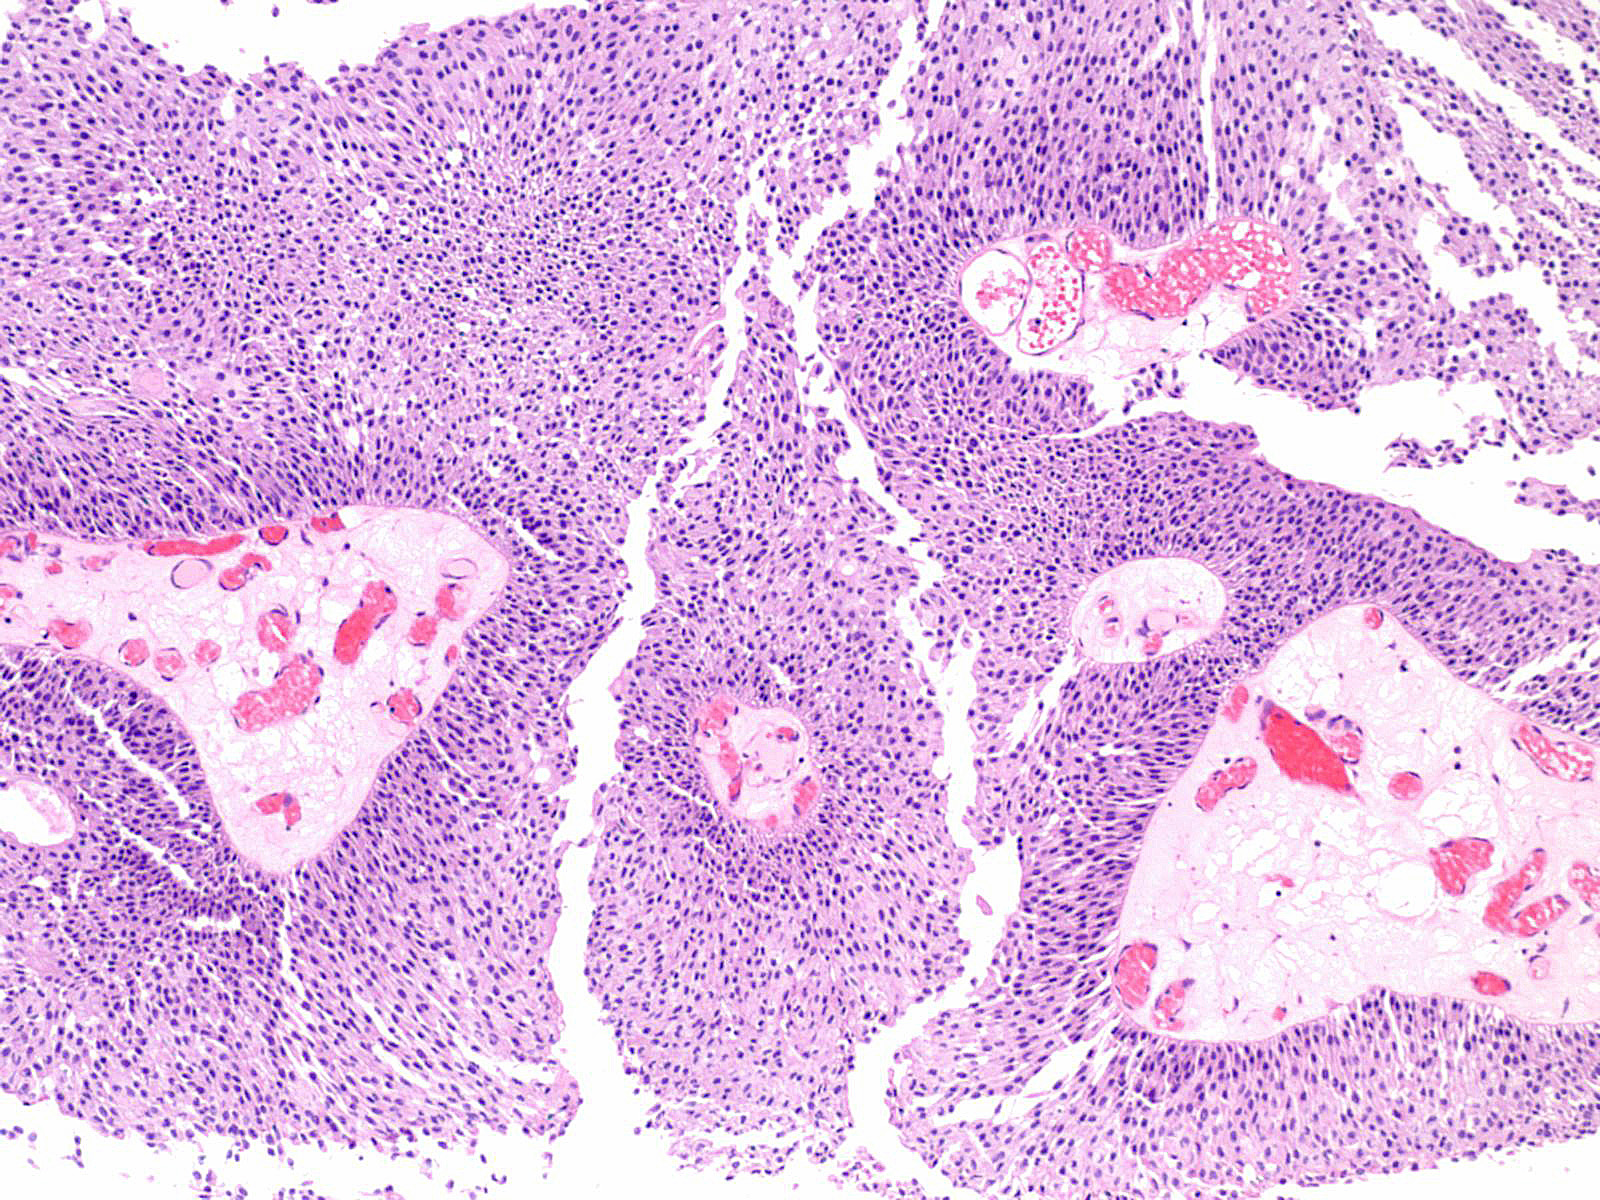

Consensus grade: Low-grade papillary urothelial carcinoma (LG-PUC)

Lesion shows moderate variation in nuclear size, shape and chromatin. Scattered nuclei are significantly enlarged and hyperchromatic relative to other nuclei. Lesion still maintains an overall orderly appearance.